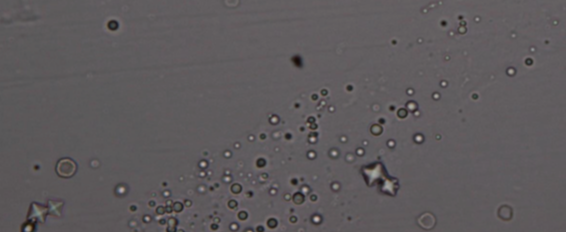

Urinalysis- Sediment

Lipid

Struvite Crystals